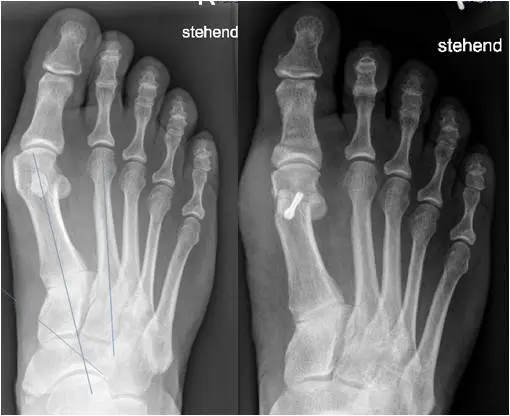

Die bildgebende Diagnostik umfasst ein Röntgenbild im dorso-plantaren Strahlengang des belasteten Fußes. Auf der dorso-plantaren belasteten Aufnahme können der Winkel zwischen dem Metatarsale I und II (Intermetatarsal Winkel) und der Winkel zwischen Metatarsale und Großzehe (HV Winkel) bestimmt werden. Zudem können die Kongruenz des Großzehengrundgelenkes bzw. die Stellung der Sesambeine beurteilt werden. Weitere Aufnahmen sind in der Regel nicht erforderlich. Schrägaufnahmen oder schnittbildgebende Verfahren wie eine MRT oder CT Untersuchung bleiben besonderen Fragestellungen vorbehalten.

Osteotomien bezeichnen die Durchtrennungen und Umstellungen von Knochen. Sie können an der Basis der Großzehe, am zehenseitigen (distalen) Mittelfußknochen am Schaft des Mittelfußknochens oder an der Basis des Mittelfußknochens einzeln oder in Kombination durchgeführt werden. Die Verschiebung und Fixation des Knochens in korrigierter Stellung soll eine dauerhaften Umstellung erzielen. Eine der häufigsten Osteotomien ist die Chevron- und die Akin- Osteotomie. Osteotomien werden häufig mit Weichteileingriffen kombiniert.

Eine übermäßige Beweglichkeit im ersten Mittelfußgelenk (TMT-I Gelenk) bei gleichzeitiger Achsabweichung des Mittelfußknochens kann mittels einer TMT I-Gelenk oder sog. Lapidus Arthrodese behandelt werden. Die TMT I Arthrodese wird auch häufig bei sehr schweren Hallux valgus Stadien angewendet. Sie kann mit anderen Techniken, wie Osteotomien oder Weichteileingriffen kombiniert werden.